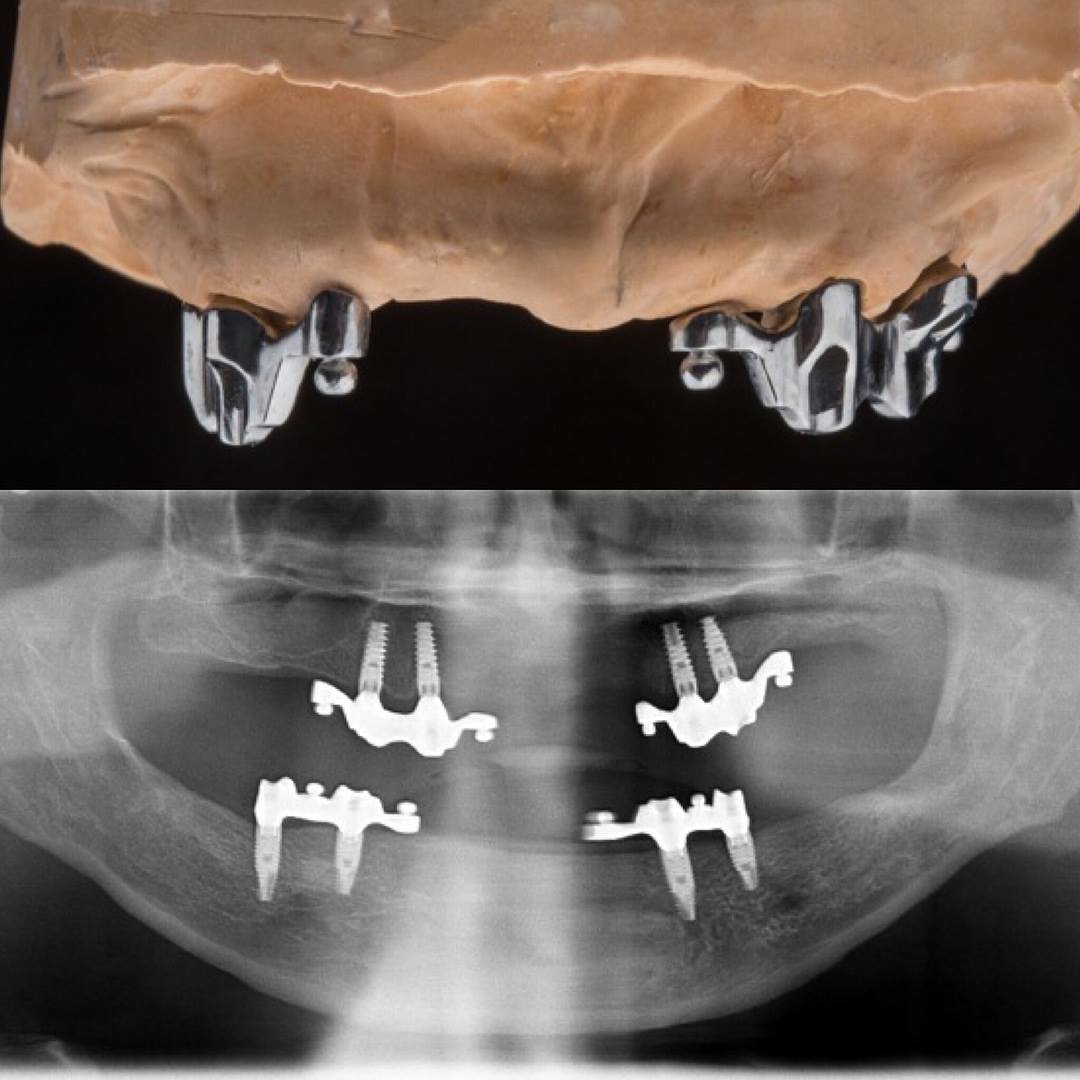

Dr. Ricardo Velázquez García es un dentista destacado en Colima, especializado en implantes dentales y cuidado integral de la salud bucal. Ubicado en el Centro Médico Puerta de Hierro, en Calle Ignacio Sandoval 1699-Consultorio 312, Girasoles, ofrece un ambiente profesional y acogedor para todos sus pacientes. Con una sólida reputación respaldada por una calificación de 5 estrellas basada en 235 opiniones, el Dr. Velázquez se distingue por su atención personalizada y la calidad de sus tratamientos. Sus pacientes valoran especialmente la amabilidad del equipo, la limpieza profunda y los resultados efectivos, como blanqueamientos dentales y procedimientos de bonding. La clínica cuenta con tecnología avanzada y un equipo comprometido en brindar una experiencia cómoda y segura. Para agendar una cita o solicitar información, puede comunicarse al teléfono 312 688 2357 o visitar su sitio web oficial https://dentaldesign.acecli.cloud/. El Dr. Ricardo Velázquez García es una opción confiable para quienes buscan mejorar su sonrisa y mantener una salud dental óptima en Colima.

Dr. Ricardo Velazquez García is a highly regarded dentist in Colima, specializing in dental implants and comprehensive oral health care. Located at Centro Medico Puerta de Hierro, Calle Ignacio Sandoval 1699-Consultorio 312, Girasoles, the clinic provides a professional and welcoming environment for all patients. With a 5-star Google rating from 235 reviews, Dr. Velazquez is known for his personalized approach and high-quality dental treatments. Patients appreciate the friendly and professional staff, thorough cleanings, and effective results including teeth whitening and bonding procedures. The clinic is equipped with advanced technology and a team dedicated to delivering a comfortable and safe experience. To schedule an appointment or request more information, contact the office at 312 688 2357 or visit the official website at https://dentaldesign.acecli.cloud/. Dr. Ricardo Velazquez García is a trusted choice for those seeking to improve their smile and maintain excellent dental health in Colima.